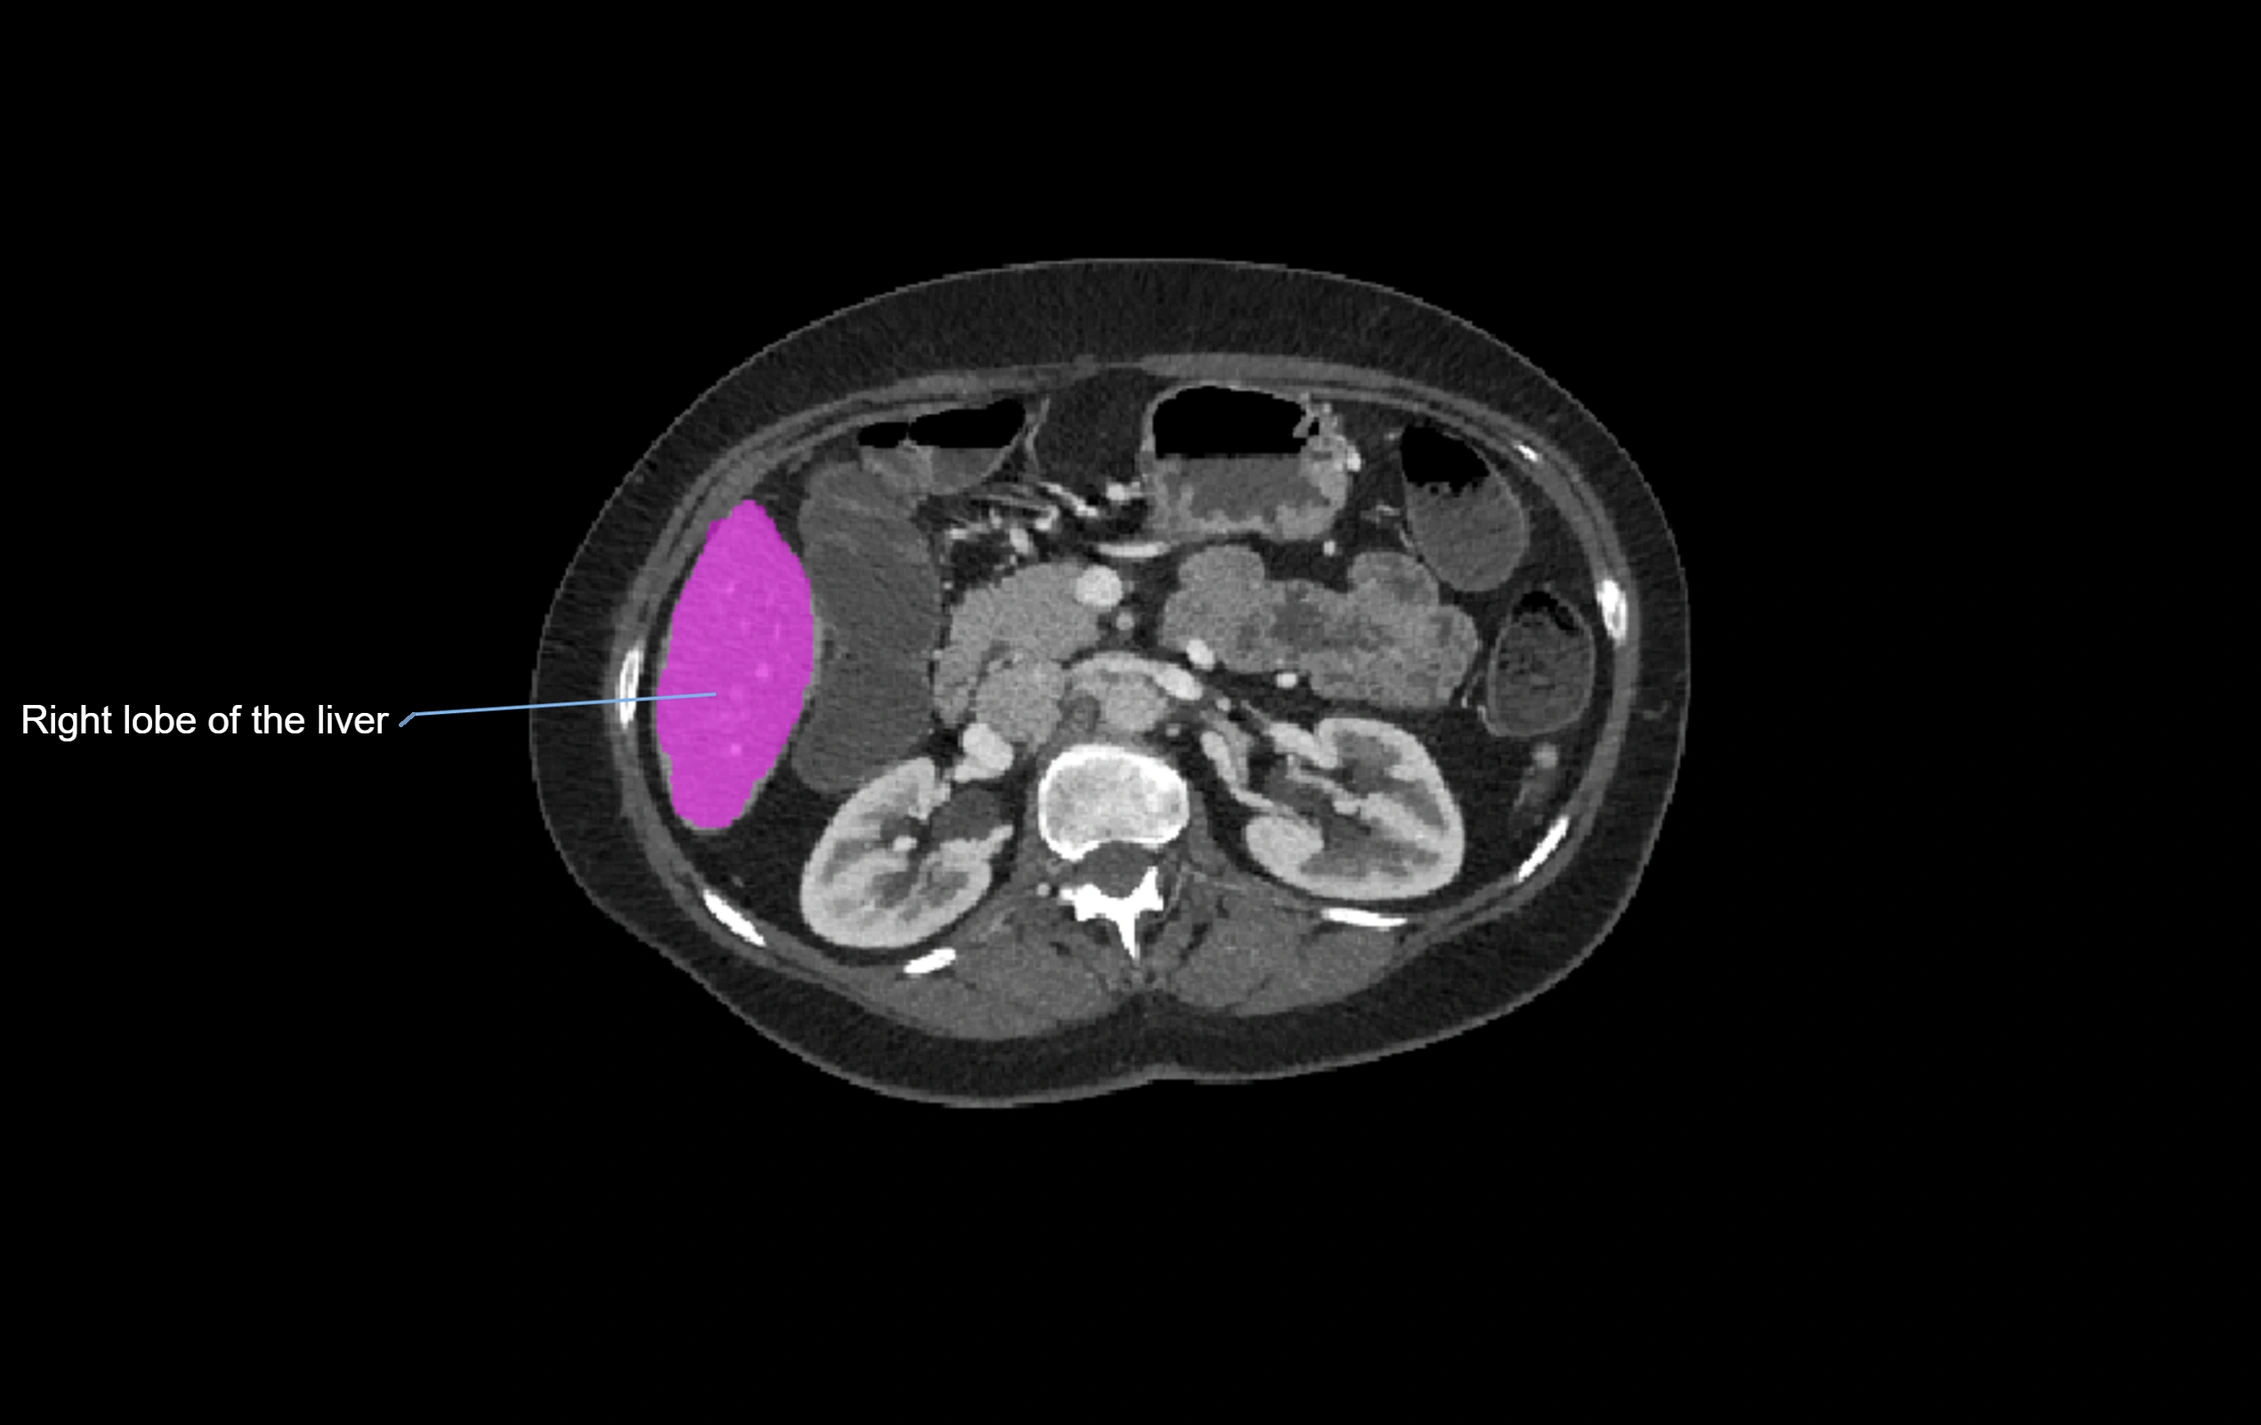

CT Image

image